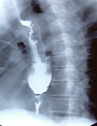

Postoperative barium esophagography. Smooth passage of contrast through the myotomy site (Courtesy Dr. V. Penopoulos)